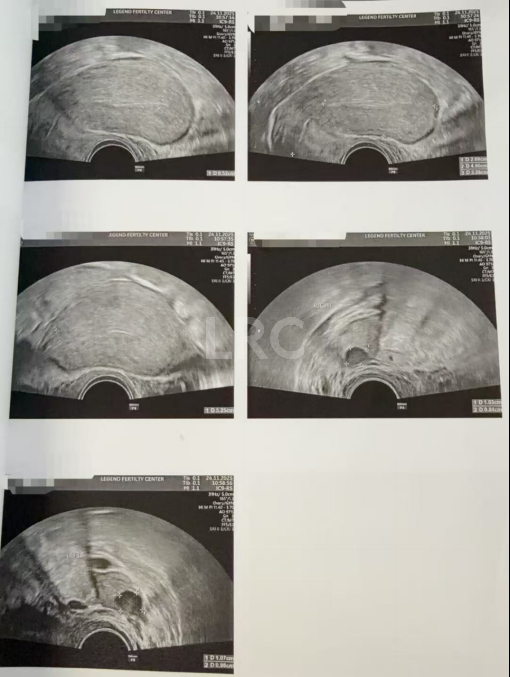

促排第七天

阴超检查:

- 右侧卵泡 9 颗可用 (20,17,16,16,15,15,13,13,12mm)

- 左侧卵泡 2 颗 (15,19mm)

子宫内膜厚度:10 mm

促排第八天

- 右侧卵泡 9 颗可用 (22,21,19,19,17,17,17,15,15mm)

- 左侧卵泡 1 颗 (19mm)

子宫内膜厚度:8.3 mm